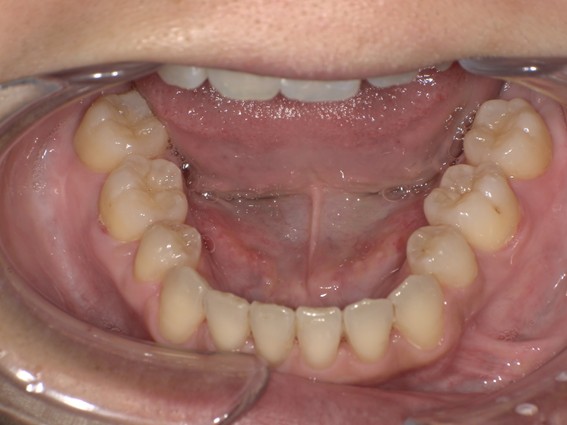

| 主訴 | 前歯が逆に噛んでいる。 |

| 治療内容 | 表側ワイヤー矯正、ジルコニア補綴を行いました。 |

| 治療費 | ワイヤー矯正660,000円(税込) ジルコニア176,000円(88,000円×2歯)(税込) |

| 治療期間 | 30ヶ月 |

| 治療回数 | 30回 |

| 想定されたリスク | 歯根吸収、歯髄壊死、歯髄充血、歯肉退縮のリスクがありました。 |

骨格性Ⅲ級・前歯部反対咬合の症例でした。反対咬合のまま治療していた前歯のサイズ不調和を、表側ワイヤー矯正とプロビジョナルクラウンで調整。正中を整え、犬歯・臼歯ともⅠ級、適切なオーバージェット(上下前歯の前後的な距離)・オーバーバイト(上下前歯の垂直的な重なり)に仕上げました。